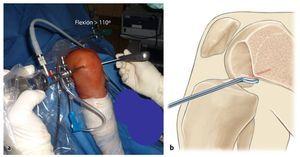

- Un soporte para piernas eléctrico permite el movimiento de la pierna y facilita la intervención (fig. 2). Este soporte permite la fijación segura de la pierna y el ajuste de diferentes ángulos de flexión.

Fig. 1 La pierna se posiciona sobre un soporte para pierna móvil eléctrico, que permite una fijación segura de la pierna en diferentes ángulos de flexión. Para practicar el túnel femoral es necesaria una flexión de más de 110º. El túnel tibial se prepara con una flexión de 30º. La intervención se realiza bajo isquemia. Para ello, se debe colocar un manguito neumático en el muslo (flecha), prestando atención de no colocarlo demasiado hacia distal, puesto que, en este caso, existe el peligro de perforarlo con la guía durante la realización del túnel femoral. Además, un manguito posicionado demasiado hacia distal puede dificultar la extracción del tendón semitendinoso.

Fig. 2 Para la cirugía de reemplazo artroscópica del ligamento cruzado anterior son necesarios dos abordajes artroscópicos hacia la articulación de la rodilla. La extracción del tendón se realiza a través de una incisión oblicua de 3 cm de longitud aproximadamente, medial a la tuberosidad tibial (fig. 5). A través de este abordaje se realiza también la perforación del túnel tibial. El artroscopio se introduce a través de un portal anterolateral alto (A). El portal anterolateral alto ofrece un buen ángulo de visión sin que los cuerpos adiposos infrapatelares puedan desplazarse por delante del artroscopio. A través del portal medial (B) se realiza la preparación de la inserción femoral del LCA y se perfora también el túnel femoral. A través de un portal anteromedial alto (C) el proceso de perforación se puede controlar mediante artroscopia. Otras intervenciones adicionales en el menisco se pueden realizar a través del portal medial. En caso de que la accesibilidad del menisco sea difícil a través de este portal, serán necesarios otros abordajes (línea).

- Si la flexión de la rodilla es mayor a 110º, puede resultar más difícil tener visibilidad sobre la zona de inserción femoral del LCA. En la técnica de perforación anteromedial la rodilla debe posicionarse en un mayor grado de flexión, por lo que los cuerpos adiposos infrapatelares se ven desplazados hacia la fosa intercondílea.